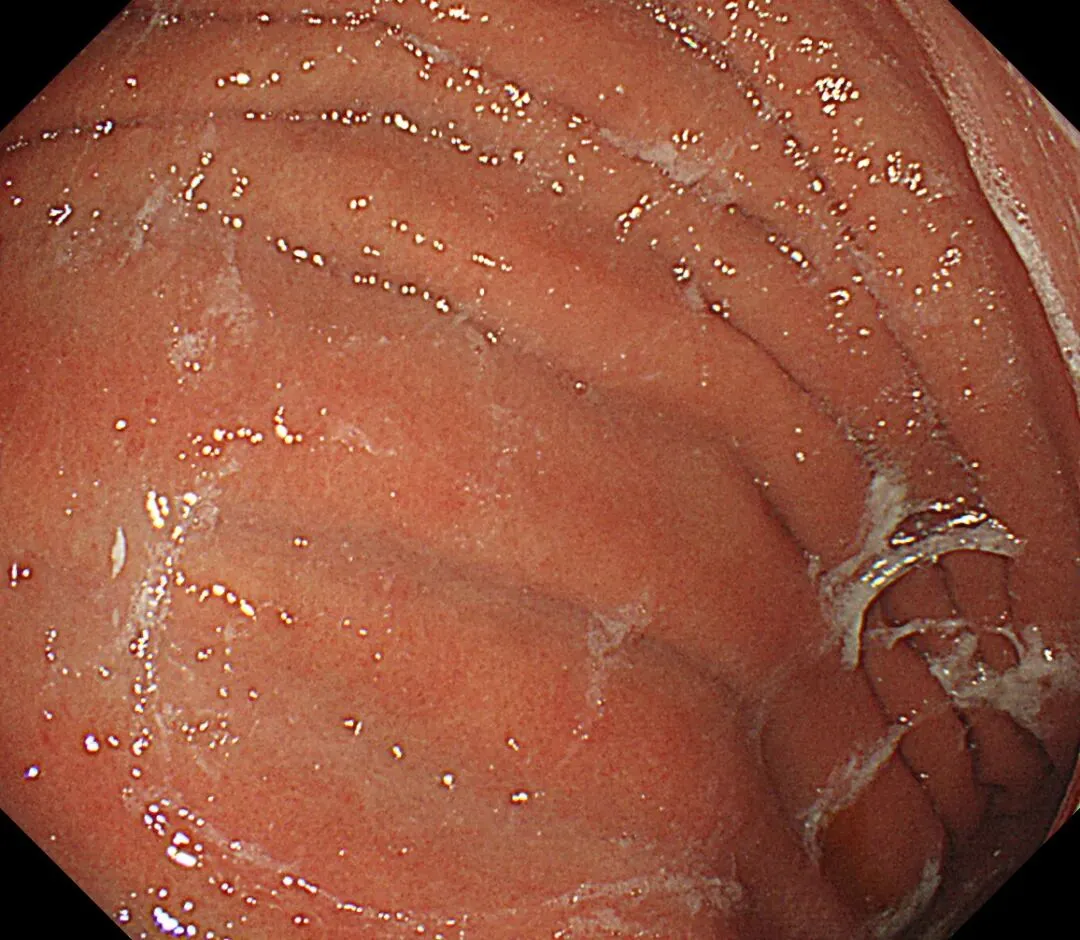

蛛网状黏液case2,服用P-CAB药物)👇

(报道称黏膜斑状或线状发红也是P-CAB药物所致,原因不明